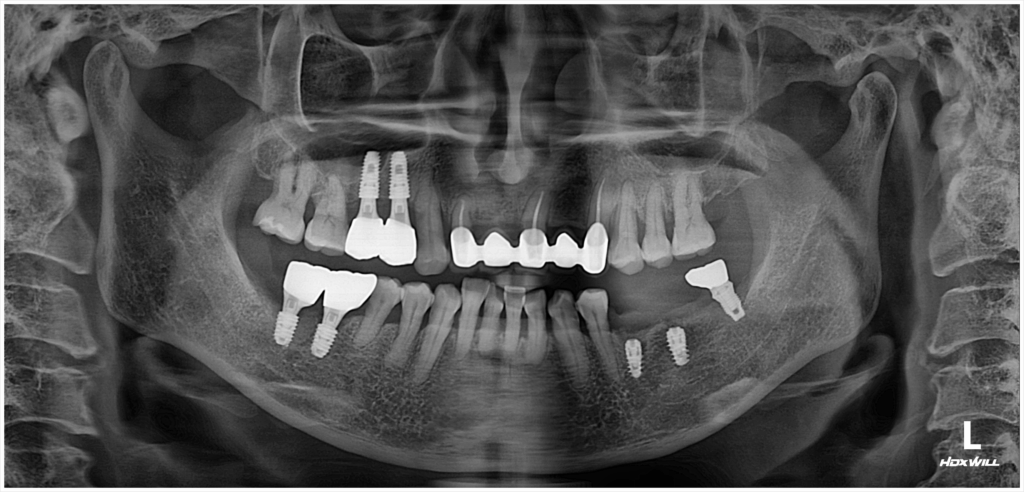

술후 사진

2025.06.02

상단의 맞물리는 치아와의 정밀한 비교를 통해, 임플란트가 목표 위치에 안정적으로 자리잡았음을 확인할 수 있었습니다.이후 경과 관찰을 통해 발치 부위의 조직 회복과 임플란트 주위의 골 유착 상태를 함께 체크했으며, 전반적인 회복 상태가 매우 양호하다는 결과를 얻을 수 있었습니다. 현재까지 특별한 문제 없이 회복이 잘 진행되고 있고, 앞으로의 치료 단계 역시 무리 없이 진행될 것으로 보입니다.

발치 후 즉시 임플란트는 시술자가 치조골 상태와 발치 과정, 보철 계획까지 정밀하게 고려해야 성공률이 높아집니다. 따라서 단순히 시술 가능 여부만 따지기보다는, 나에게 맞는 방식인지 충분한 설명을 듣고 결정하는 것이 중요합니다. 영도치과서울화이트S치과에서는 환자 개개인의 구강 상태에 맞춘 맞춤 진료를 통해 보다 효율적인 임플란트 치료를 진행하고 있습니다.